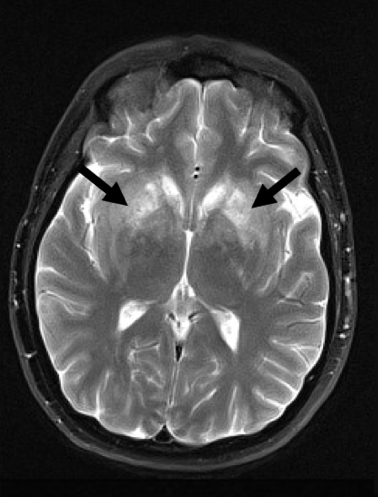

Steroid-Responsive Encephalopathy Associated With Autoimmune ...

CASE REPORT Steroid-Responsive Encephalopathy Associated with Autoimmune Thyroiditis Presenting with Diffusion MR Imaging Changes C. Grommes C. Griffin ... Retrieve Content

Steroid-responsive encephalopathy Associated With Hashimoto ...

CASE REPORT Steroid-responsive encephalopathy associated with Hashimoto thyroiditis Petra Zimmermann & Enno Stranzinger Received: 17 May 2011 /Revised: 19 September 2011 /Accepted: 24 September 2011 /Published online: 30 December 2011 ... Access Doc